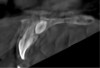

Fig 19. CBCT scan of an implant guide made with biocompatible resin on a low-cost LCD 3D printer (100 μm offset, 100 μm resolution). Note the increased air gap between the guide and the stone model on the left side of the image.

Figure 19

Fig 20. CBCT scan of the same guide shown in Fig 19 manufactured with PLA on a low-cost FFF 3D printer (100 μm offset, 100 μm resolution). Note that the air gap appears larger indicating a poorer fit of the guide on the stone model.

Figure 20